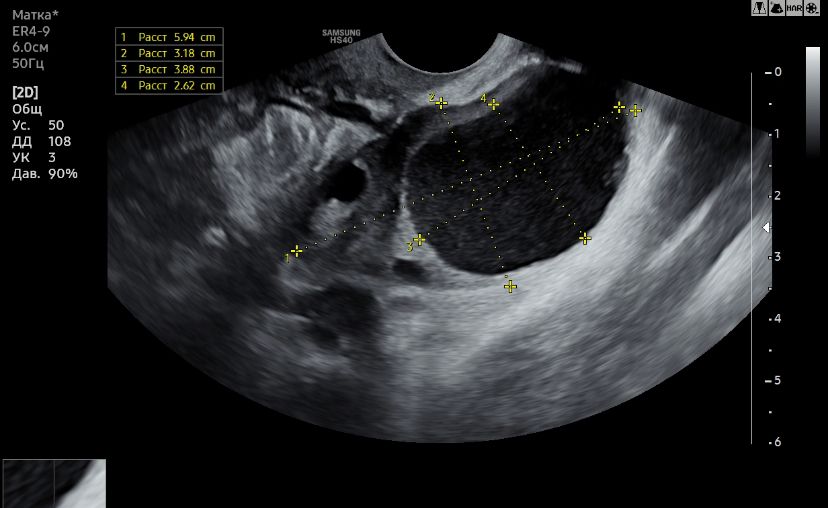

Узи и киста

Сказали киста желтого тела, но я не сильно доверяю, до этого она говорила что обычная киста от фоллика